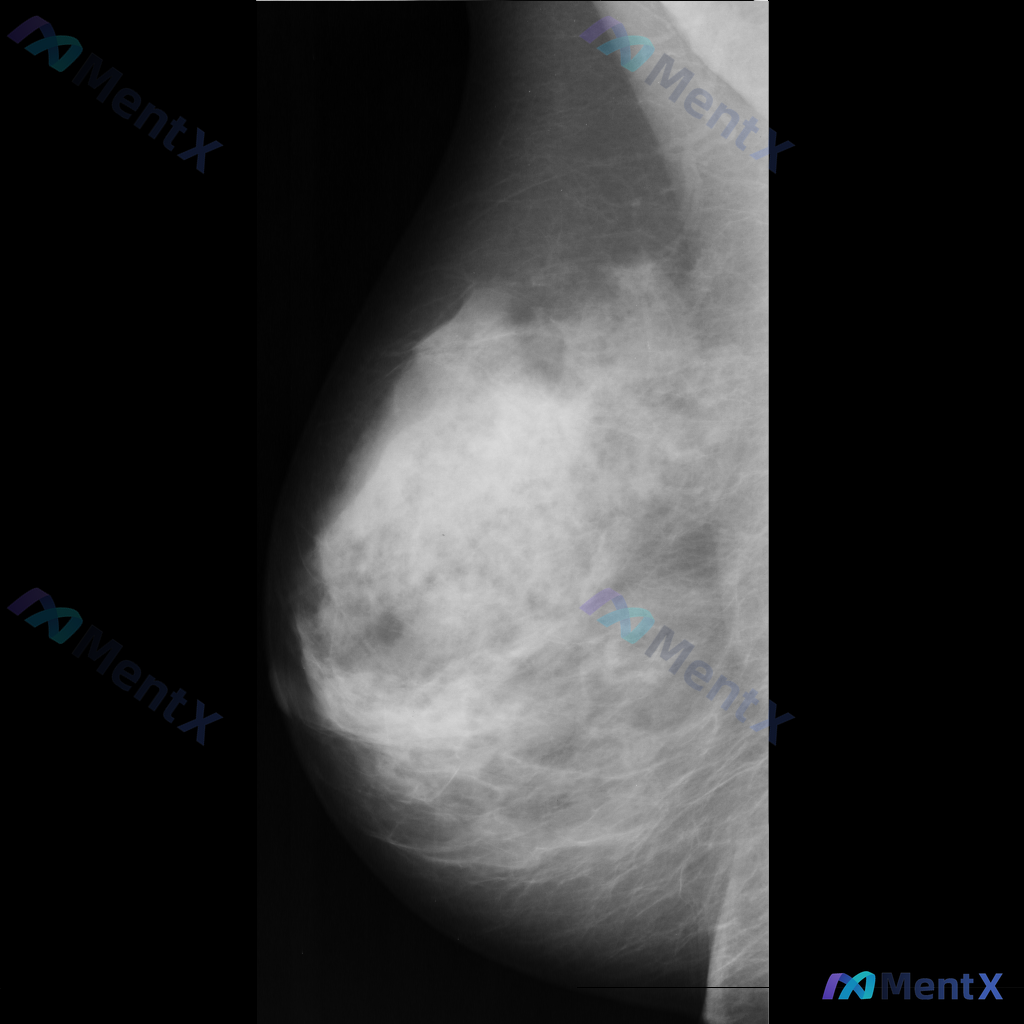

这张乳腺钼靶片的异常表现,你会先往哪个方向考虑?

整理了一份乳腺病例,先放核心资料出来大家讨论: 56岁女性,因发现左乳肿块1周就诊,肿块无痛且进行性增大,既往病史无特殊,有30年吸烟史。 查体:双侧乳房均可触及无压痛、活动性差的小结节。 乳腺钼靶证实肿块存在,细针抽吸细胞学检查提示:可见恶性细胞排列成一排。 现在问题来了:只看这些信息,你认为最可...